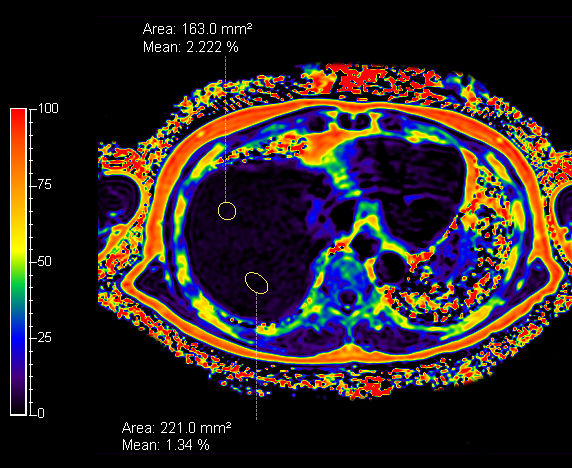

mDIXON Quant (fat percentage) - Breath hold